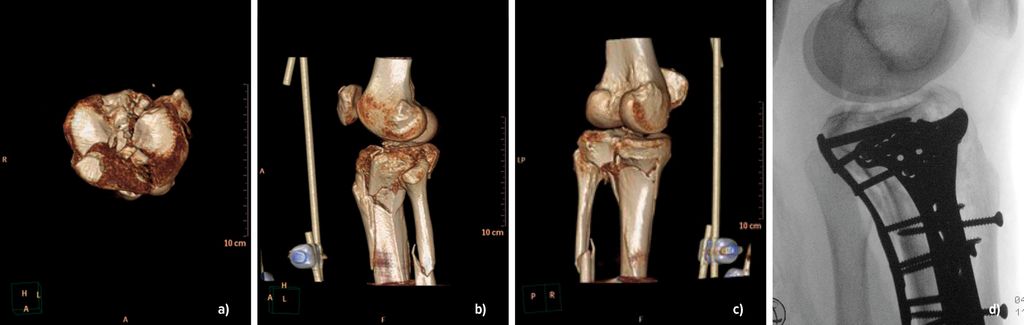

Die Wahl des Zugangs richtet sich strikt nach der Frakturmorphologie. Da das laterale Tibiaplateau in ca. 75–80% der Fälle betroffen ist, stellt der anterolaterale Zugang den Standard dar. Er erlaubt eine gute Sicht auf das vordere Drittel des Plateaus, ist jedoch für posterolaterale Segmente unzureichend. Hier kann der posterolaterale Zugang nach Frosch als weichteilschonender Weg ohne Fibulaosteotomie angewandt werden (Abb.3). Gerade bei posterioren Fragmenten kann die indirekte Reposition durch den ventralen Standardzugang unzureichend sein; der dorsale Zugang kann eine direkte Sicht, eine stabile Abstützosteosynthese und die Schonung neurovaskulärer Strukturen ermöglichen. Der anteriore mediale Zugang ist geeignet für seltene isolierte mediale Frakturen oder im Rahmen bikondylärer Versorgungen. Seltener finden der posteromediale Zugang nach Lobenhoffer (Rekonstruktion der medialen Säule) und der erweiterte laterale Zugang Anwendung bei großen zentralen Trümmerzonen.

Abb. 3: Präoperative CT-basierte Planung mittels 3D-Rekonstruktion des Kniegelenkes bei angelegtem Fixateur externe (a–c) und anschließende Versorgung mit medialer, lateraler und posteriorer Platte (d)